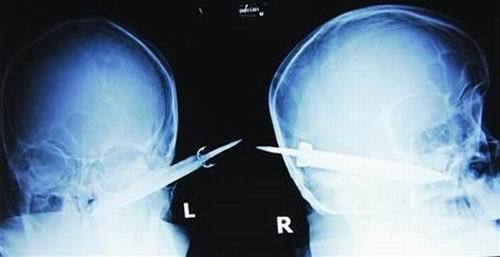

經(jīng)過檢查,醫(yī)生說這把長有10厘米左右的刀,從右耳窩上前方直接刺進(jìn)了鼻腔,離頜內(nèi)大動(dòng)脈很近,刀卡在了骨頭中,要取出這把刀最怕大出血,萬幸的是這把三棱刀并沒有傷及大腦。

截至昨晚11時(shí)30分,患者頭部刀經(jīng)手術(shù)已取出,生命體征平穩(wěn)。(芮瀟瀟)